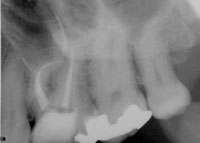

The case was completed, and a beautifully shaped and cleaned root canal was achieved (Figure 4). It should be noted that while many clinicians take both a preoperative and postoperative radiograph, it is the author’s opinion that an intermediate radiograph also be taken prior to completion of the root canal. This does not need to be a master-file radiograph; rather, a master-cone radiograph will suffice as confirmation that adequate length control was achieved (Figure 5 and Figure 6). The purpose for this is to allow the clinician to correct any discrepancies within the canal system prior to obturating the canal. By taking a master-cone radiograph, the clinician can see that the length is accurate and can avoid having a completed case that was obturated short because the cone was accidentally bent when it was placed into the canal.

Figure 4 Postoperative radiograph showing successful root canal.